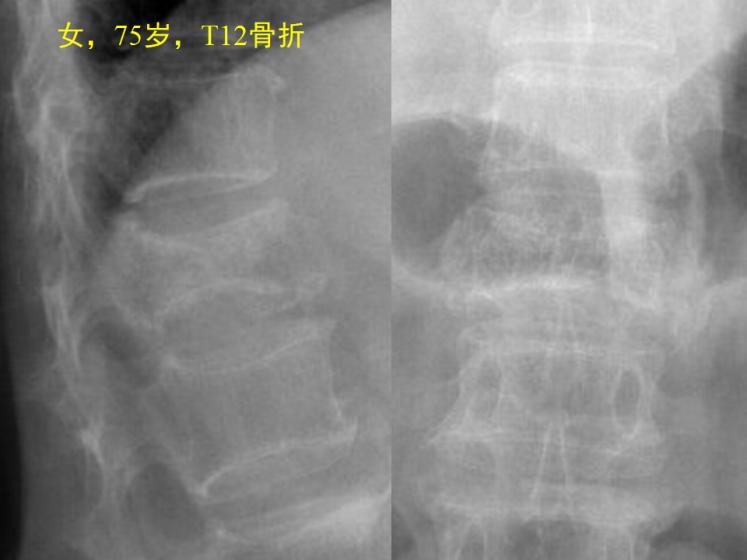

张阿姨75岁,最近1周腰背部疼痛,也没摔着磕着;躺着不动时还行,一翻身或起床就疼的利害,非要有人扶一把才行。儿女带她上医院,没想到医生一拍片子,竟然是脊柱压缩性骨折!

图片1.jpg

其实老年人大多合并骨质疏松,很多时候没有明确的外伤也会有骨折,甚至对骨质特别疏松的患者,一个喷嚏或轻轻一个懒腰,也会导致疏松的脊椎出现压缩性骨折,就像上面张阿姨一样。